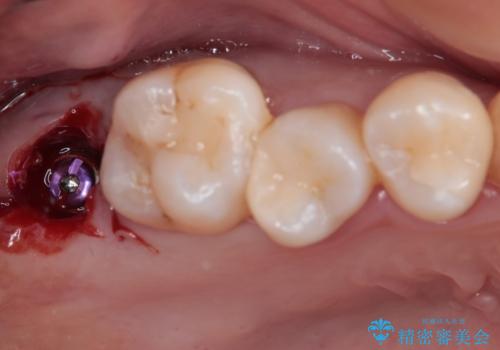

患者様と相談し、抜歯をした上でインプラントによる補綴治療を行うこととしました。

抜歯後に不快感は消失したのですが、手前の歯にあるむし歯が痛み出してきたため、セラミックインレーにて修復治療を並行して行いました。